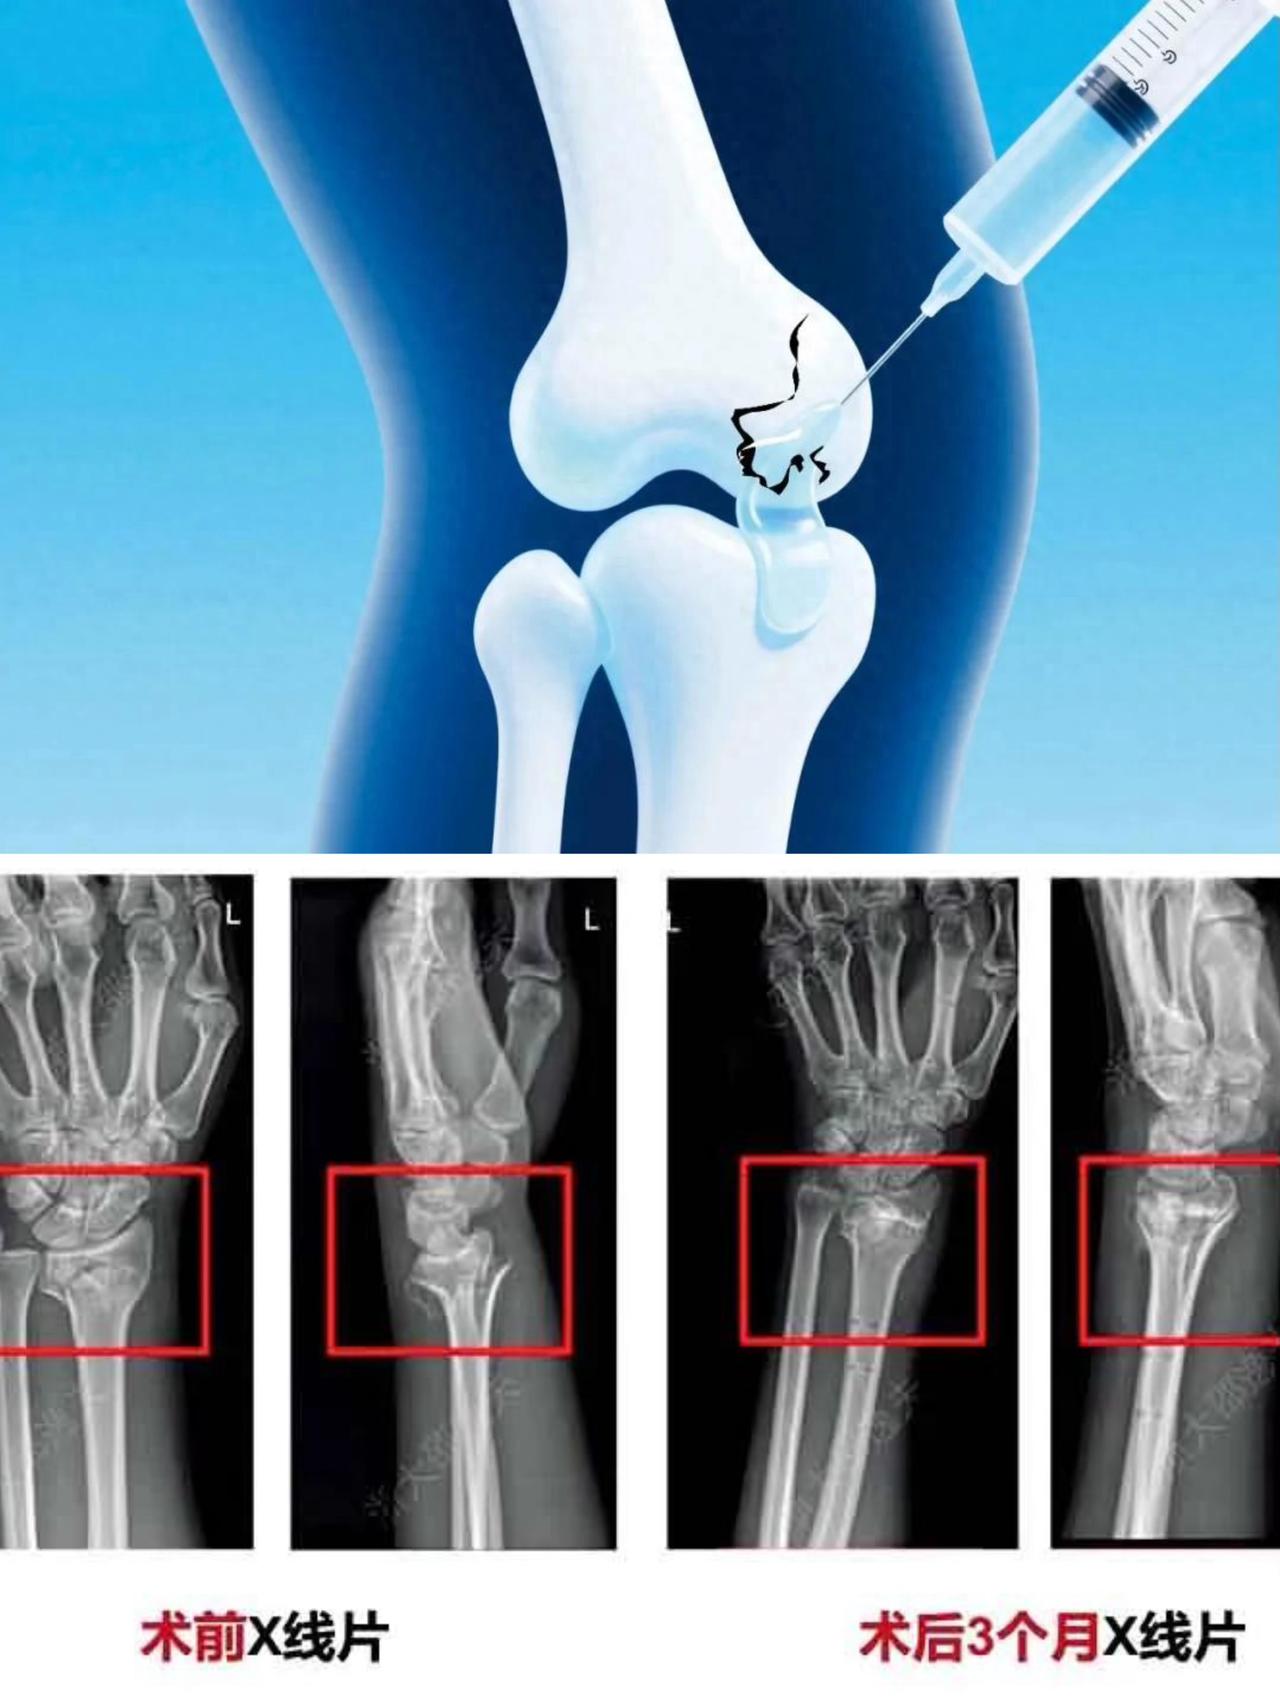

骨折治疗的新希望?“骨胶水”横空出世,为患者带来? 简单来说,“骨胶水”是一种能把骨折碎片“粘”住的医用黏合剂,它的目标是替代或补充传统的钢板、螺钉,让骨折治疗更微创、更安全。 如果成功普及,患者可能会迎来这三大改变: ✅ 手术更微创,恢复更快 • 切口小,出血少,疼痛轻。 • 减少对周围组织的干扰,理论上能更快康复。 ✅ 告别二次手术的烦恼 • 理想的骨胶水能被人体逐渐吸收。 • 患者再也不用为取钢板、螺钉而经历第二次手术。 ⚠️ 风险与挑战依然存在 • 技术难度大:既要粘得牢,又要能被吸收,还要能促进骨头生长,要求非常苛刻。 • 审批周期长:作为最高风险的第三类医疗器械,从临床试验到上市通常需要多年时间。 • 效果有待验证:目前还缺乏大规模、长期的临床数据来证明它能在所有类型的骨折中都优于传统方法。 总而言之,“骨胶水”代表了骨科的一个重要发展方向,尤其在某些特定类型的骨折上展现出巨大潜力。但它要真正走进千家万户,成为常规治疗手段,恐怕还需要我们耐心等待。